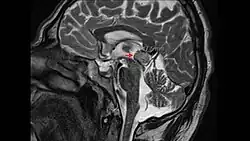

Le germinome pinéal est une forme rare de tumeur cérébrale, touchant principalement les adolescents de sexe masculin. Elle se caractérise par une lésion siégeant le plus souvent autour du troisième ventricule cérébral et touche souvent la glande pinéale elle-même, ainsi que le compartiment supra-sellaire. En fonction de la zone touchée, les symptômes peuvent comprendre l'hydrocéphalie, des troubles visuels (diplopie par exemple), acouphènes, et anomalies endocriniennes. Leur taux de survie à 10 ans est de plus de 90%[1]

Le diagnostic repose en premier lieu sur l'IRM du cerveau, puis le type histologique[8] de la tumeur est précisé par une biopsie stéréotaxique, réalisée par un neurochirurgien. On profite généralement de cette opération pour réaliser, en plus une ventriculocisternostomie[8], pour permettre l'écoulement du liquide cérébro-spinal, ou liquide céphalo-rachidien en ancienne nomenclature. Ce geste est essentiel pour réduire l'HTIC, qui demeure une urgence médico-chirurgicale.